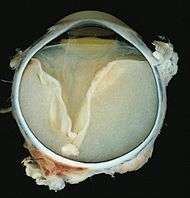

Grossly, retinal detachment and yellowish subretinal exudate containing cholesterol crystals are commonly seen.

Microscopically, the wall of retinal vessels may be thickened in some cases, while in other cases the wall may be thinned with irregular dilatation of the lumen.[9] The subretinal exudate consists of cholesterol crystals, macrophages laden with cholesterol and pigment, erythrocytes, and hemosiderin.[10] A granulomatous reaction, induced by the exudate, may be seen with the retina.[11] Portions of the retina may develop gliosis as a response to injury.